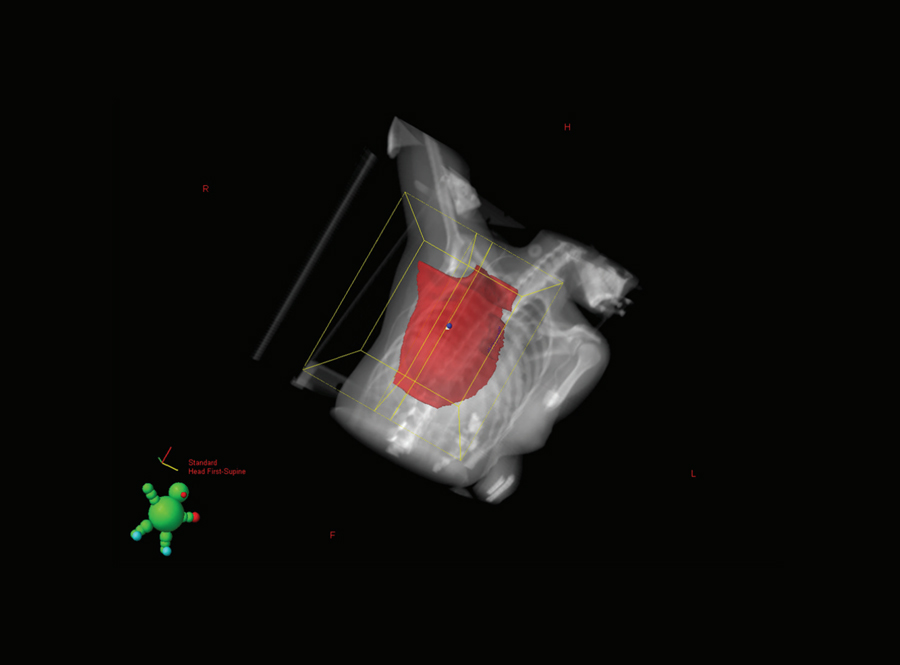

一种用来尽量减少器官暴露于不必要辐射的技术是深吸气屏息(DIBH)。DIBH是一种与传统3D适形放疗相结合的治疗乳腺癌的技术。在这种技术中,患者深呼吸,增加胸壁和心脏之间的距离,扩大肺容量,以及增加治疗区域和其他正常组织之间的距离。由于病人会屏住呼吸,这也有助于他们在放射过程中保持静止。

杜曼和同事博士最近发表了一项研究调查DIBH在使用VMAT时减少低剂量暴露于降低临界器官的临界器官,以及使用VMAT的其余部分。在该研究中重点的患者经历了含有组织膨胀器或永久性植入物的乳房切除术,并在传统的3D全成形技术中提供解剖学复合物的治疗解剖学复合物。因此,VMAT是这些患者的首选,因为3D技术将在高剂量辐射暴露的显着风险下将其关键的器官置于其临界器官。

在研究中,预先确定了左侧乳腺癌这样的患者进行了研究。为了量化使用VMAT的DIBH减少低剂量暴露,计算患者的辐射剂量,并比较两种不同模式,即自由或常规呼吸和DIBH获得的CT扫描。在Dibh期间,妇女被要求在20秒内深呼吸约20秒,在他们的模拟和治疗之前在家练习这一点,以提高他们呼吸呼吸并最大化肺部的能力的能力和信心并持有大呼吸。

使用VMAT和DIBH的组合将辐射减少到心脏和肺部分别30%和11%,并将对侧乳腺/植入物分18%。

Dumane博士总结道,由于复杂的解剖结构,当需要植入物重建也需要局部淋巴结放疗的乳腺癌患者接受VMAT治疗时,应该考虑DIBH。VMAT和DIBH联合使用,对心脏和肺的辐射分别减少了30%和11%,对侧乳房/植入物的辐射减少了18%。这表明使用呼吸是有益的,应该考虑到治疗计划为这个病人组,特别是限于没有风险,和治疗中心与机器配置为使用这项技术应该不需要更多的专门培训或资源。